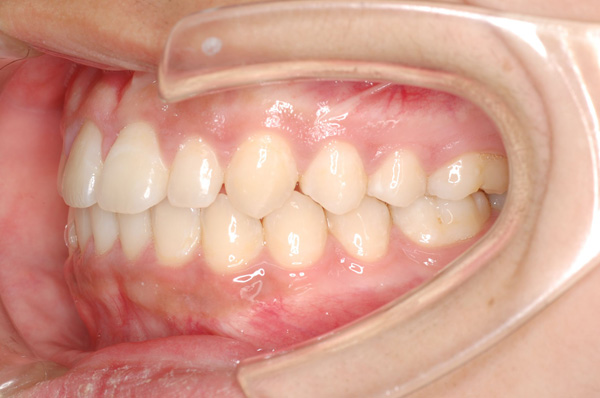

臼歯部における横方向の咬合関係の異常は、上歯列弓の相対的な狭窄が原因で起こる舌側交叉咬合(lingual crossbite)と、下顎に比べ相対的に大きい上顎のために生じた頬側交叉咬合(buccal crossbite)に分けられる。舌側交叉咬合の方が、頬側交叉咬合よりも多い。 また、舌側交叉咬合は片側性交叉咬合と両側性交叉咬合に分類することがあるが、はっきりとした片側性交叉咬合は通常、上歯列の両側性の狭窄と下顎の交叉咬合側への変位を示す。